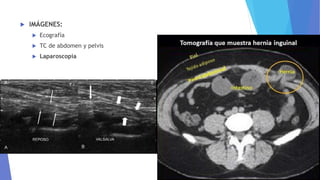

 IMÁGENES:

 Ecografía

 TC de abdomen y pelvis

 Laparoscopía